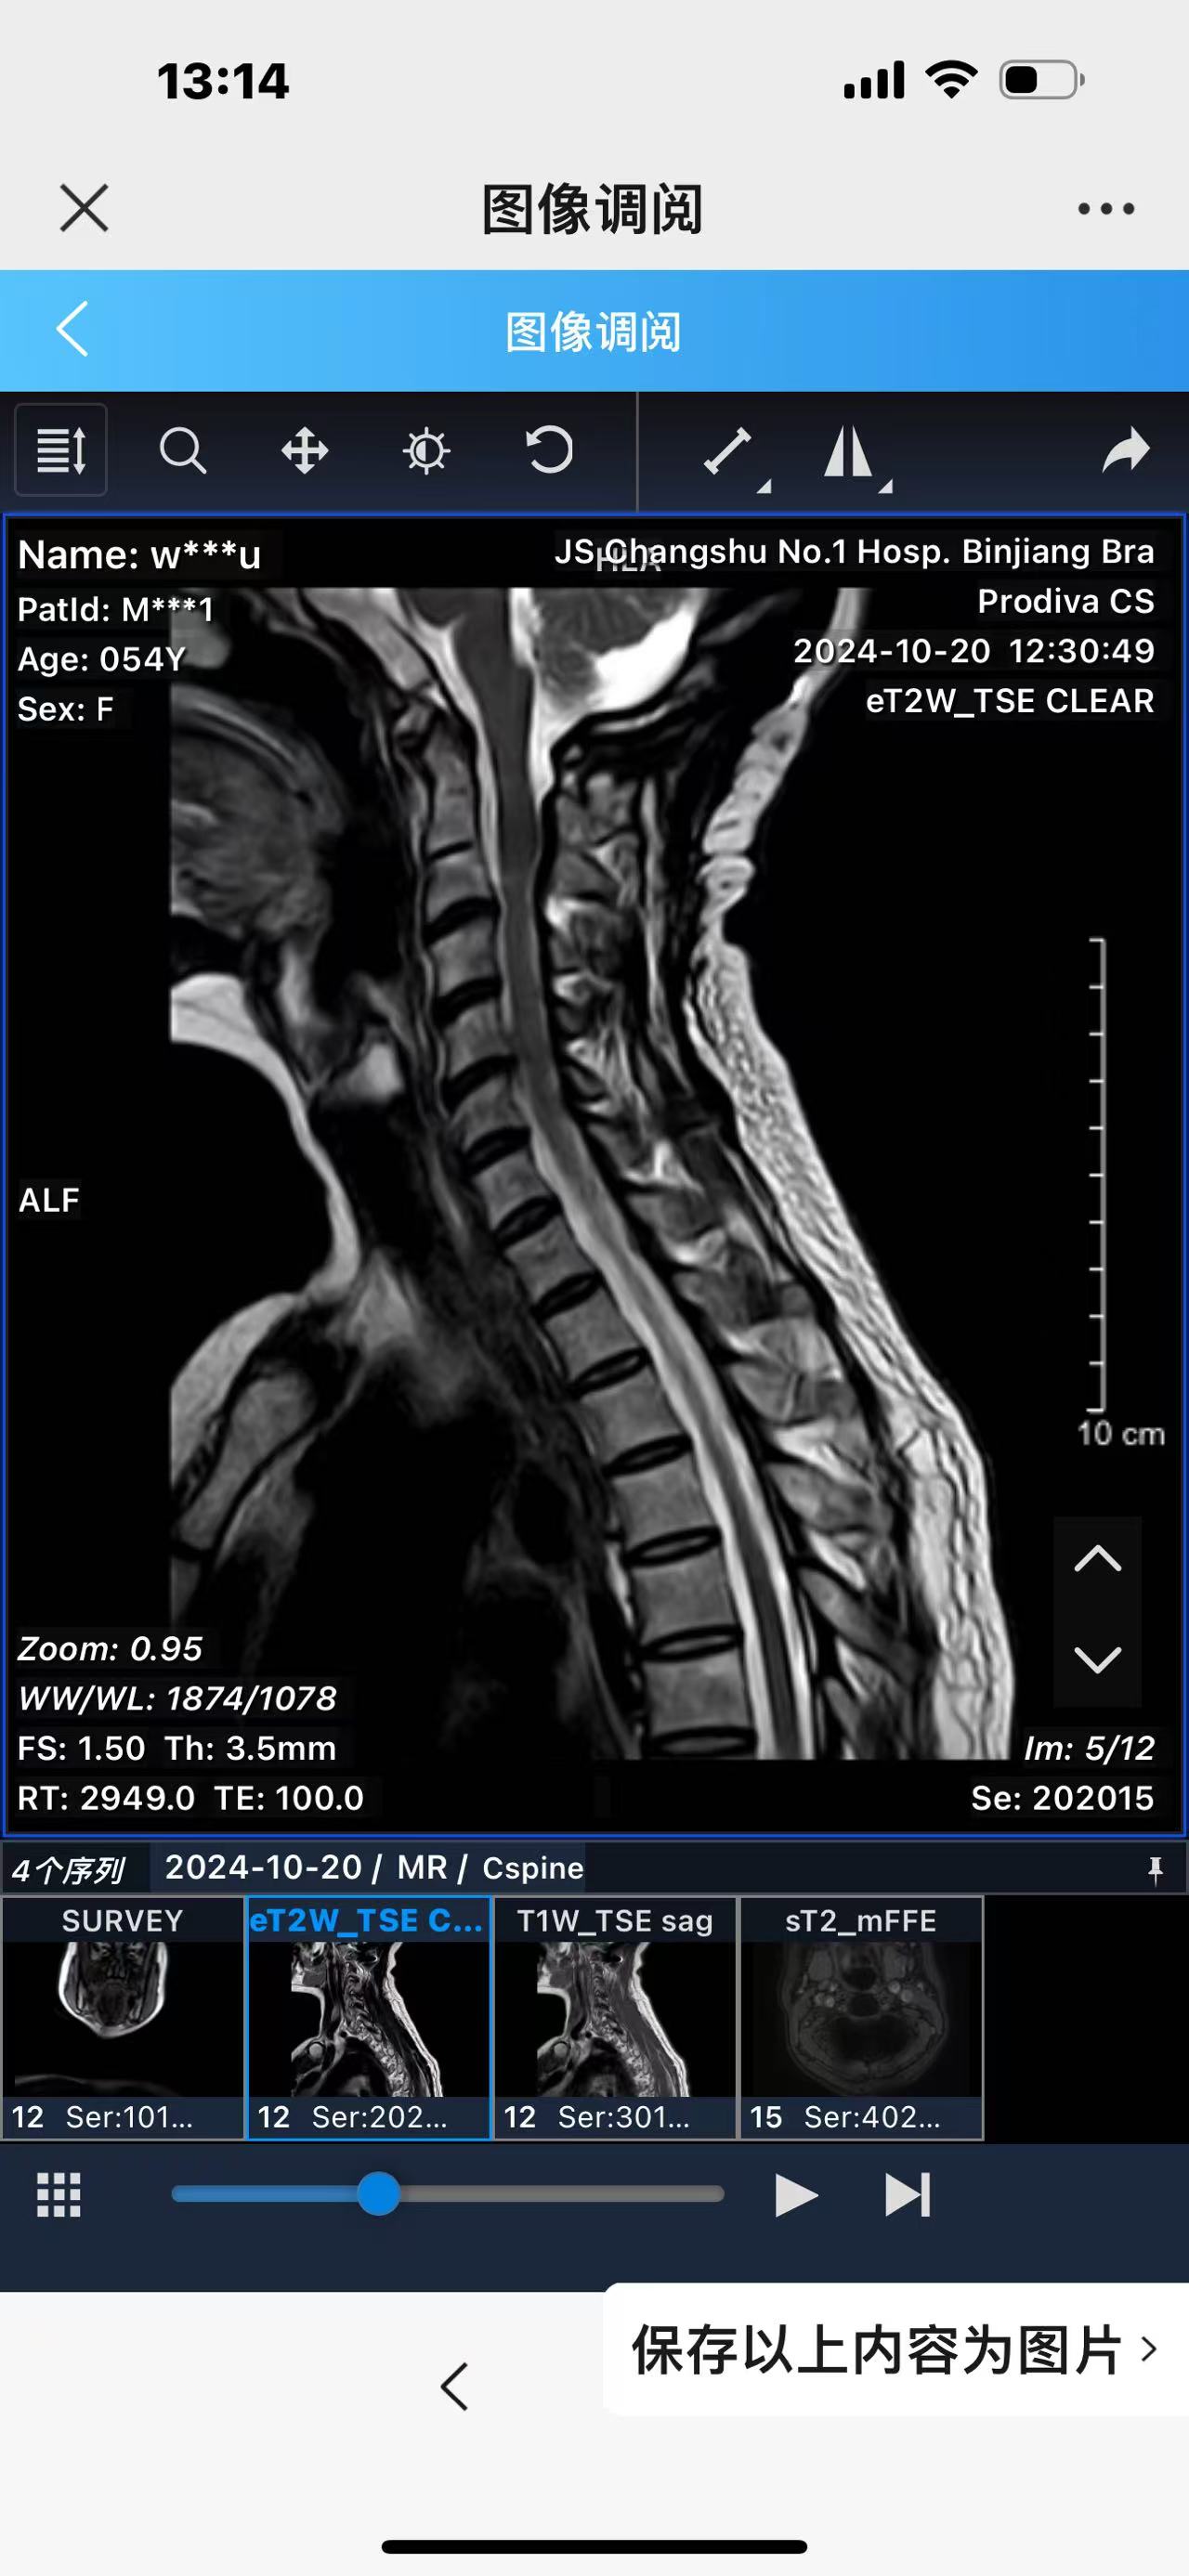

• 诊断:寰枢椎脱位,颅底凹陷

• 术后影像:

• 2024.10.20,复查,对位良好,偶尔会肩甲骨酸,坐下就不酸。